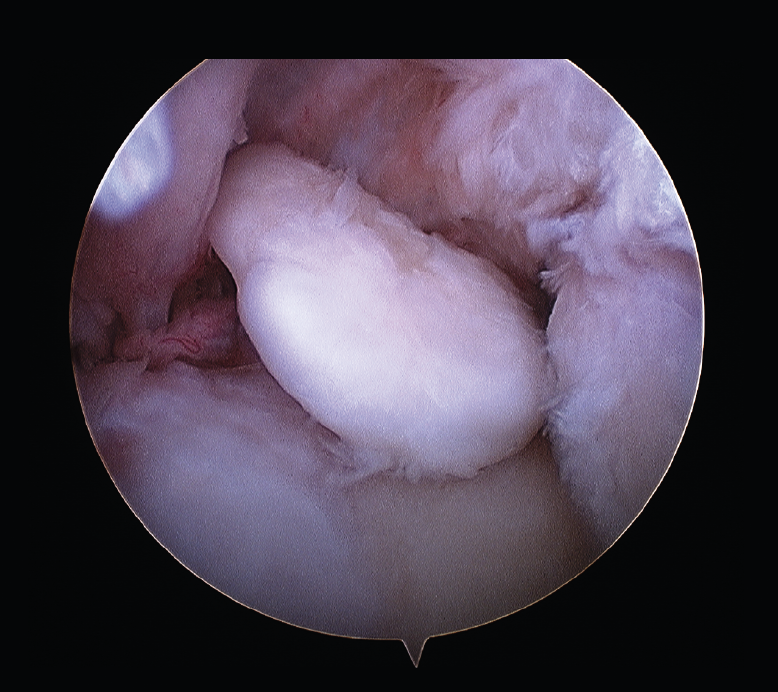

Los estudios de imagen para evaluar un codo rígido deben ser, en primer lugar, unas radiografías simples, que incluyan proyecciones anteroposterior, lateral y 2 oblicuas. Si se requieren más detalles de la superficie articular, se debe realizar una tomografía computarizada (TC) del codo con reconstrucciones tridimensionales que ayudará en la planificación quirúrgica para eliminar osteofitos y osificaciones heterotópicas (Figura 2).

Figura 2. Fibrosis articular, degeneración del cartílago y presencia de cuerpos libres no calcificados.

La resonancia magnética (RM) puede ser útil para valorar el cartílago articular, la fibrosis articular y periarticular, el estado ligamentoso y la presencia de cuerpos libres no calcificados (Figura 3).